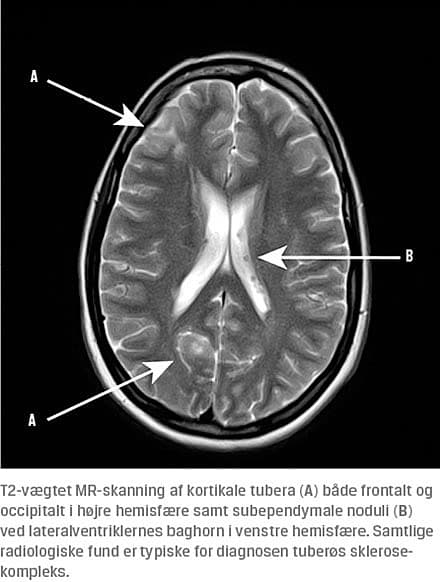

Ved den neurologiske undersøgelse fandt man normale forhold. Ved en objektiv undersøgelse blev der fundet adskillige, men diskrete angiofibromer i ansigtet og flere diskrete hypopigmenterede hudområder på arme, abdomen og ben, dog ingen fibromer ved neglene. En oftalmoskopi gav mistanke om retinale forandringer bilateralt, og ved et efterfølgende oftalmologisk tilsyn diagnosticeredes hamartomer på begge øjne. En CT af cerebrum rejste mistanke om både kortikale tubera og subependymale noduli, hvilket efterfølgende blev bekræftet ved en MR-skanning af cerebrum med kontrast. Et interiktalt elektroencefalogram viste udbredt dominant 10-11 Hz-aktivitet og ingen fokale eller paroksystiske abnormiteter. En UL-undersøgelse viste multiple angiomyolipomer i begge nyrer, hvilket blev genfundet ved MR-skanning af nyrer og abdomen, hvor man også påviste en enkelt tumor på to cm uden fedtopladning på venstre nyre. En CT af thorax viste en enkelt cyste i

behandling med lamotrigin og blev henvist til genetisk rådgivning og klinisk opfølgning. Hun opfyldte således seks ud af 11 kliniske hovedkriterier for TSC: kortikale tubera, subependymale noduli, retinale hamartomer,

renale angiomyolipomer, angiofibromer og shagreen patch.